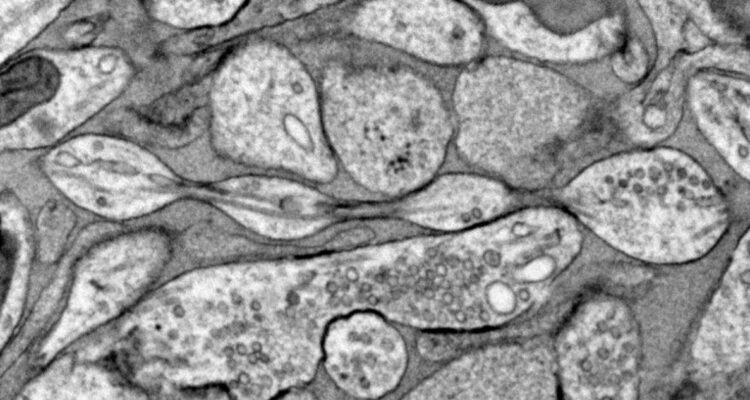

Imagen microscópica de neuronas de ratón preservadas con la técnica de congelación a alta presión | Johns Hopkins Medicine

Su estudio, basado en neuronas de ratones, encontró que los axones, que son los “brazos” que se extienden entre células cerebrales e intercambian información, no son como tubos cilíndricos, sino que podrían tener la forma de un collar de perlas.

Esta no es la primera vez que se observan axones con esa forma, de hecho, este fenómeno de inflamación se produce en las neuronas moribundas, personas con Párkinson u otras enfermedades, neurodegenerativas. Pero los ratones del estudio no presentaban estas condiciones.

Sin embargo, el método de Griswold asegura ser diferente, ya que preparó las células con una técnica de “congelación a alta presión”, que puede preservar la estructura fina de las neuronas.

Así, con un microscopio electrónico, vio que los bultos de 200 nanómetros de diámetro, distribuidos uniformemente a lo largo de los axones de los ratones, no eran como las bolitas producidas por atascos. De hecho, no tenían nada dentro.